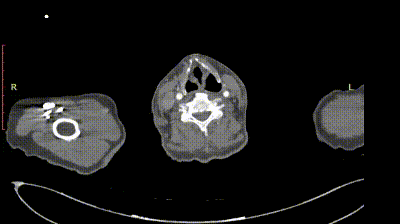

夹层动脉瘤CTA:逆撕A型主动脉夹层,升主动脉及无名动脉见夹层累及,左颈总及左锁骨下动脉烟囱支架。

术前影像